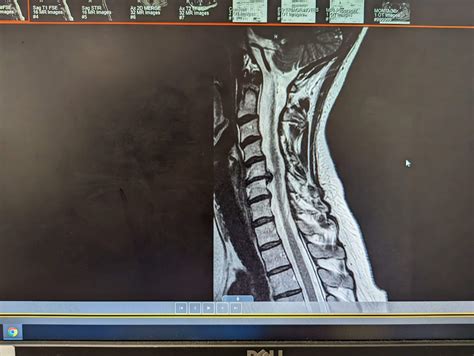

• Imaging Studies: X-rays, MRI, or CT scans are used to visualize the cervical spine and identify the extent of the disc herniation or spinal stenosis.